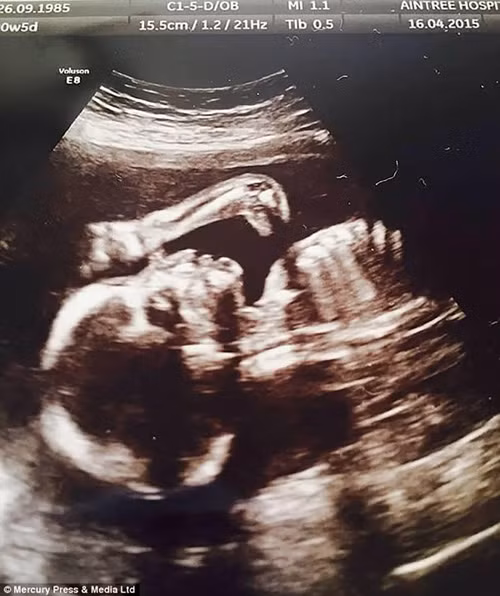

Sản phụ Lenne Sullivan đã vô cùng ngạc nhiên khi nhìn thấy hình ảnh siêu âm thai nhi cô con gái đầu lòng Ruthie-Lou 20 tuần tuổi của cô trông như một chú khủng long con sau khi chị thực hiện siêu âm tại bệnh viện.

Sản phụ 29 tuổi đến từ Liverpool nước Anh đã không hề để ý thấy sự khác lạ từ bức ảnh siêu âm sau khi trở về nhà.

Chỉ khi cô cho bạn bè và người thân xem, hình ảnh đập vào mắt đầu tiên là chiếc đầu và cổ dài giống như loài khủng long Apatosaurus, một chi khủng long Sauropoda từng sống ở Bắc Mỹ thời kỳ Jura Muộn.